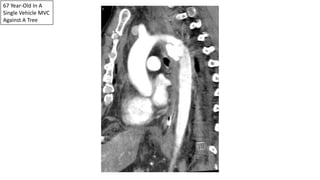

67 Year-Old In A

Single Vehicle MVC

Against A Tree

Traumatic

Pseudoaneurysm